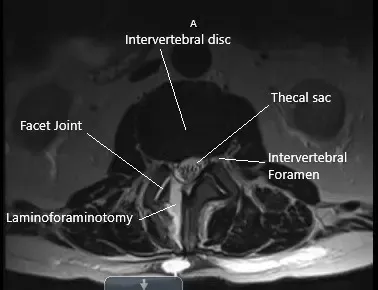

Preoperative Axial MRI section at the L2-L3 level showing herniated disc.

Physical examination corroborated with the imaging studies and the femoral traction test was positive. MRI imaging revealed diffuse disc bulge at L2-L3 and superimposed right paracentral disc herniation. A sequestrated disc herniation in the right lateral recess impinging the descending right L3 nerve root. There are a mild spinal canal and mild bilateral foraminal stenosis.